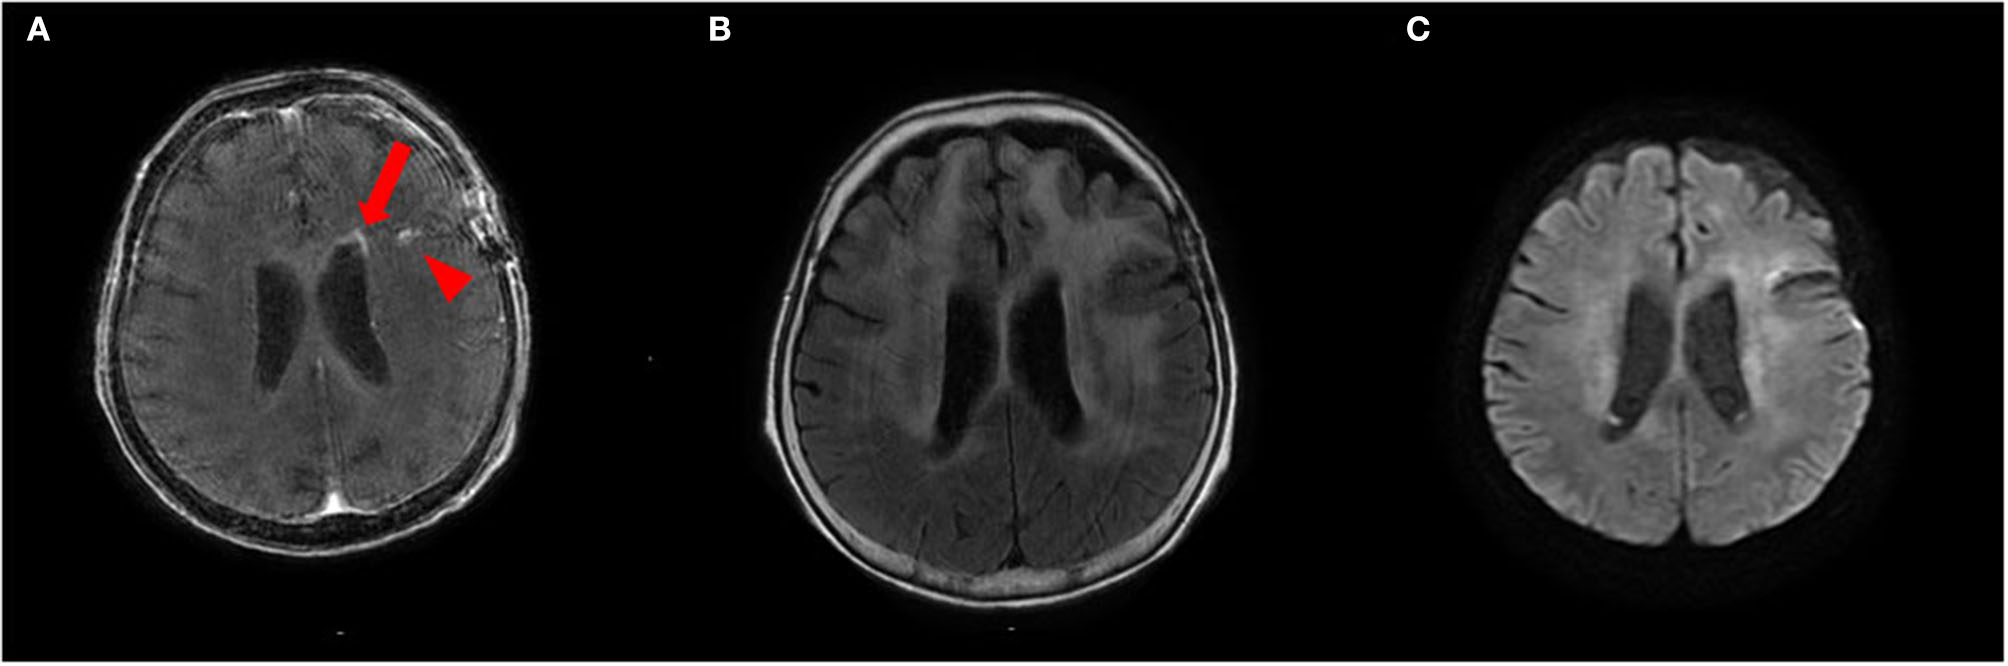

To treat LC, we administered two courses of high-dose mPSL (1,000 mg/day for 3 days), followed by 60 mg (2 mg/kg) prednisolone (PSL) for 63 days with a taper of every 5 mg for 7 days and whole cranial irradiation. Contrast-enhanced MRI performed 1 month after brain biopsy revealed a spotty gadolinium enhancement in the left periventricular white matter without high intensity on DWI (Figures 4A–C). Two months after the treatment initiation, the anti-NAE antibody was detected in the serum before mPSL treatment, revealing the presence of HE. We performed thyroid sonography, and it was characterized by isoechogenicity, very slightly internal heterogeneity, no diffuse goiter, and a few cysts (Supplementary Figure 1). Moreover, a second check showed the serum anti-TPO antibody and anti-Tg antibody to be within the RR in chemiluminescent immunoassay (0.72 and <0.50 IU/ml, respectively; RR <4.11 and <5.61 IU/ml, respectively). At that time, she recovered from the apallic syndrome, had simple conversations, and consumed food orally. However, her consciousness worsened again when PSL was reduced to 15 mg/day. No evident new abnormality, including aggravation of LC, was found on the re-performed contrast-enhanced MRI. After another high-dose mPSL therapy, her consciousness improved; therefore, we considered the re-exacerbation of her consciousness as due to HE relapse, even though we performed a third check of the serum anti-TPO and anti-Tg antibodies, which were within the RR in chemiluminescent immunoassay (0.44 and <0.50 IU/ml, respectively). Although her consciousness improved, severe cognitive impairment persisted, and she still needed careful assistance for all her daily living activities. The clinical timeline is shown in Supplementary Figure 2.

Figure 4. (A,B) Contrast-enhanced brain MRI recorded 1 month after brain biopsy shows a spotty gadolinium enhancement in the left periventricular white matter (arrow) and post-biopsy scar (arrowhead) (A) with T2 hyperintensities (B). (C) This lesion does not show abnormal hyperintensities on diffusion-weighted imaging (DWI).